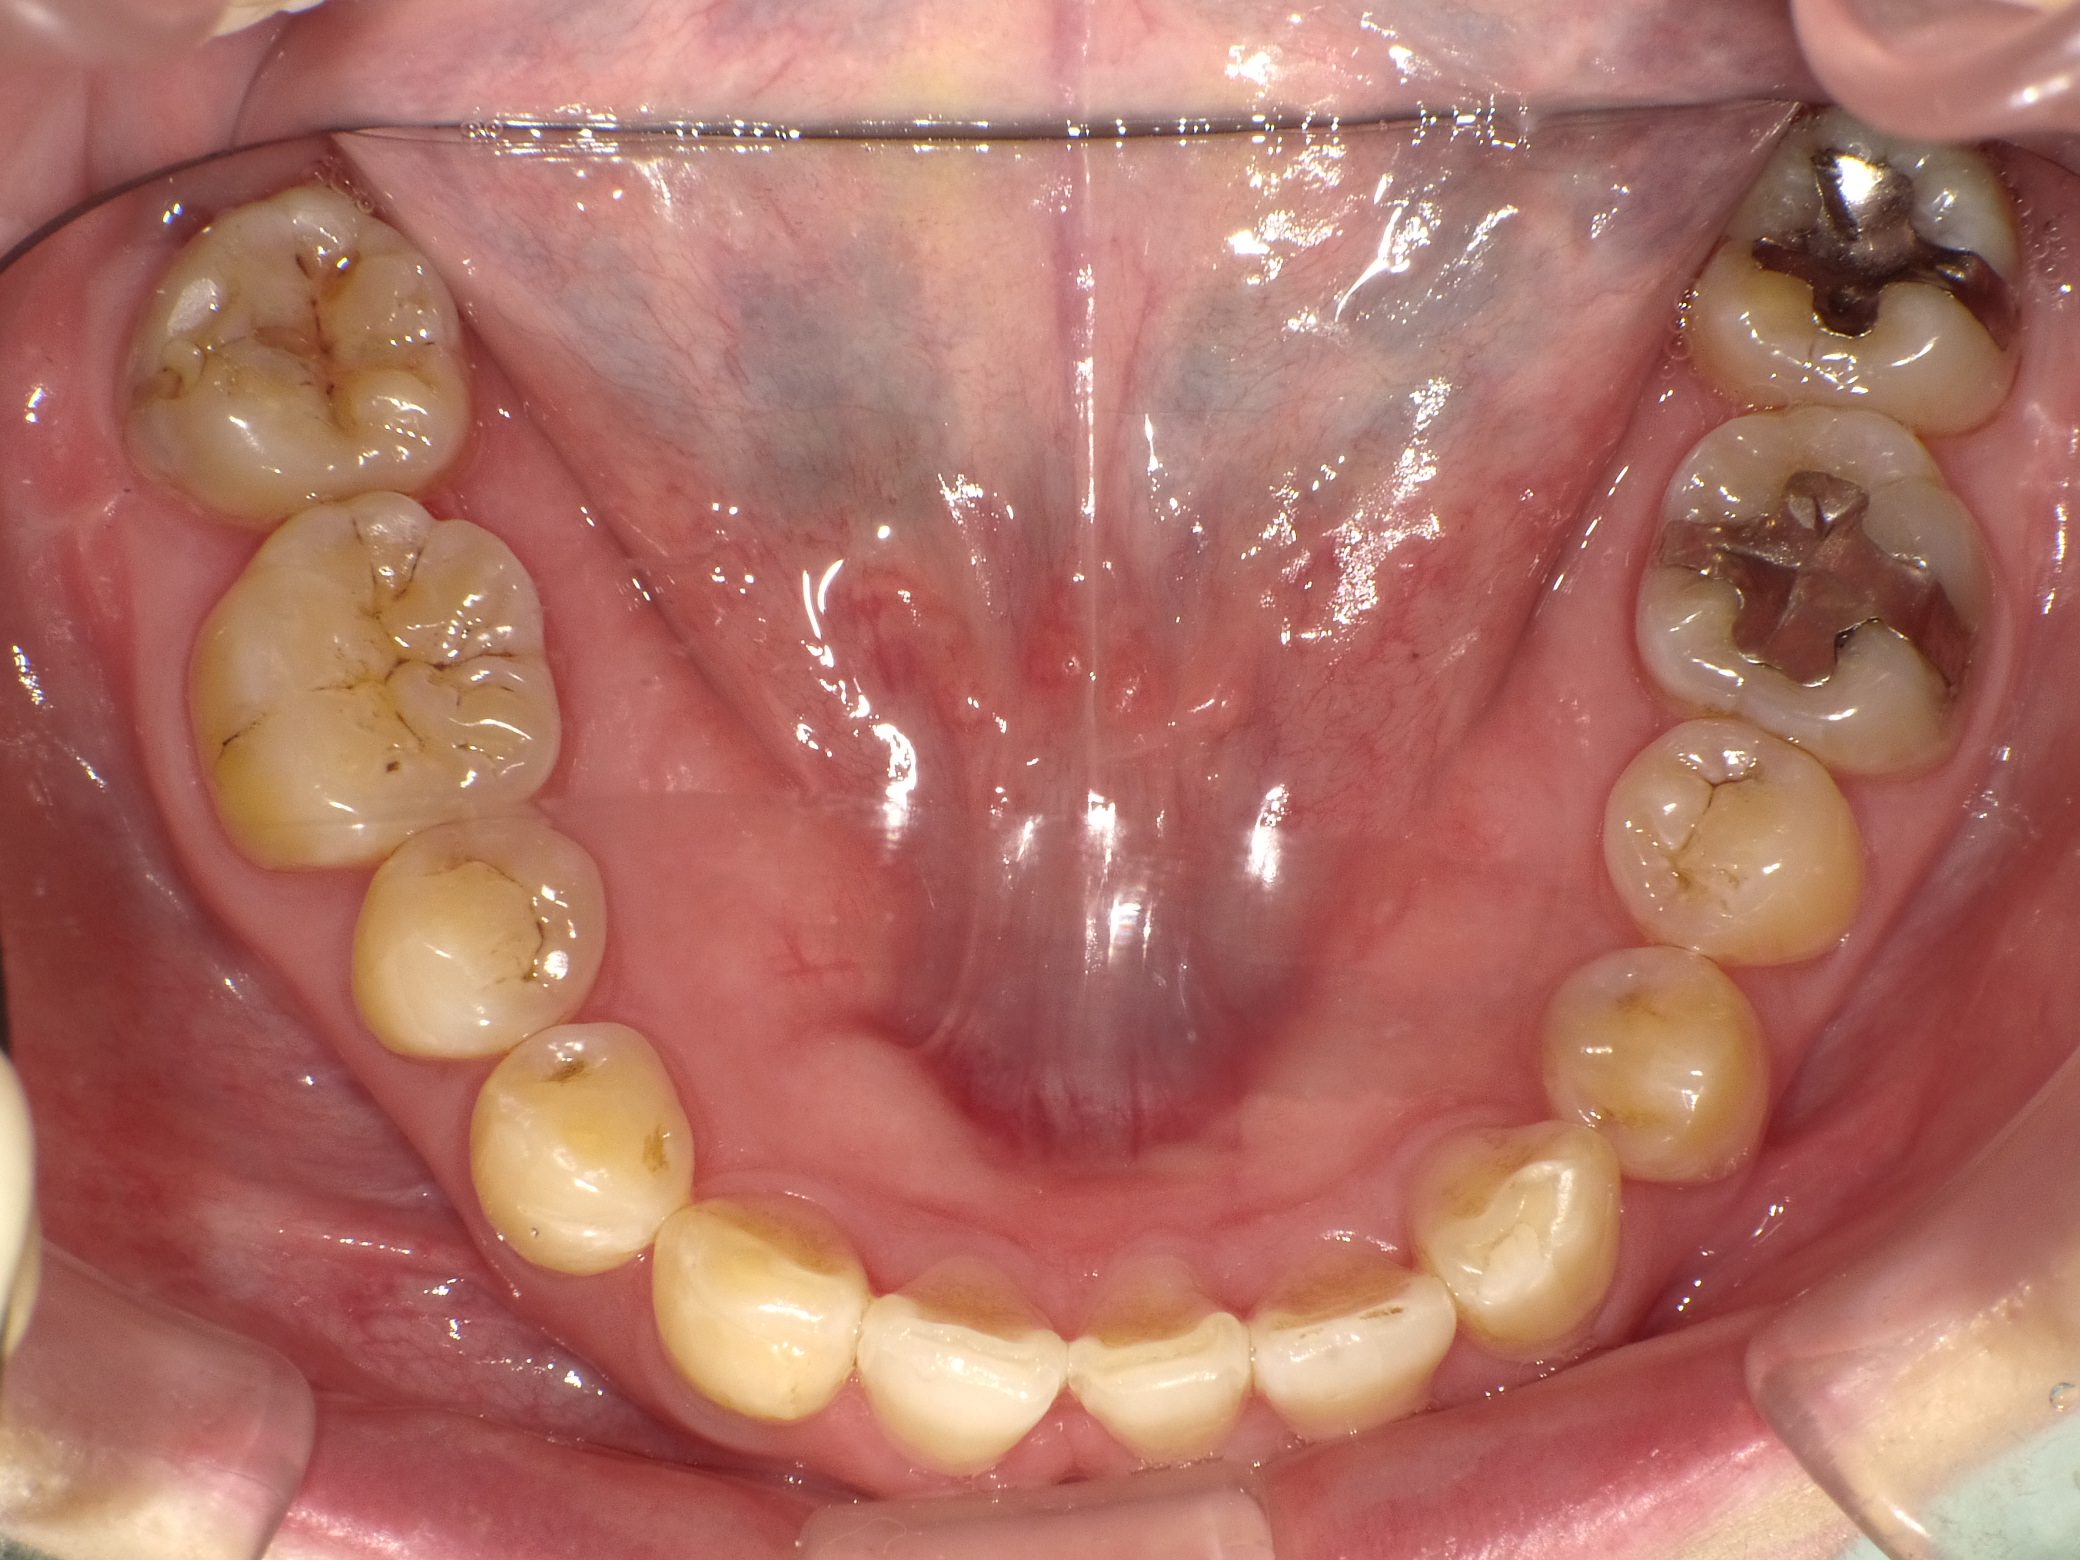

Before

After

【社会人】インビザラインフル 反対咬合(受け口)を改善 下顎前歯1本抜歯

全く装置の浮きがなくしっかり使ってくれたので2年で終了しました。

10年前の治療ですが、今もしっかり後戻りせずに歯並びを保たれています。